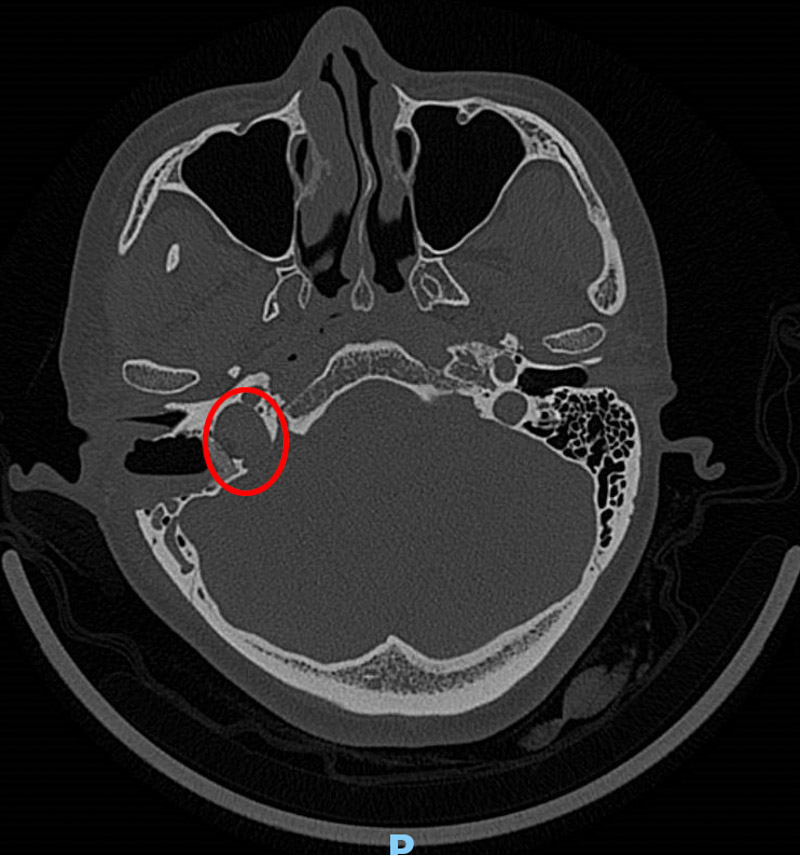

接诊医生了解情况后,为韦女士做了耳内镜及听力学检查,并没发现异常,但根据患者的实际情况并结合多年的经验判断,患者的右耳有可能患有血管搏动性耳鸣。为了进一步证实,患者进行了高分辨头颅CT检查,果不其然,放射科医生在CT影像学中发现了蛛丝马迹:患者的右侧颈静脉球高位,可疑合并前壁和外侧壁缺损。这就是导致韦女士耳鸣的罪魁祸首!

确定病因后,耳鼻咽喉科主任李纪辉立即召集团队一起为患者制定手术方案,做好一系列术前准备后,为韦女士行右侧颈静脉球还纳术进行治疗。术后一周,韦女士惊喜地发现,耳鸣的症状真的消失了!